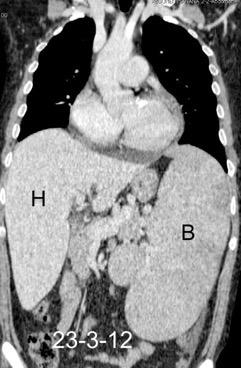

Hepatoesplenomegalia

Riñones poliquísticos

Ascitis masiva

Carcinomatosis peritoneal

Elevación bilateral por riñones poliquísticos. Hernia hiatal ¡Sin gas en abdomen!